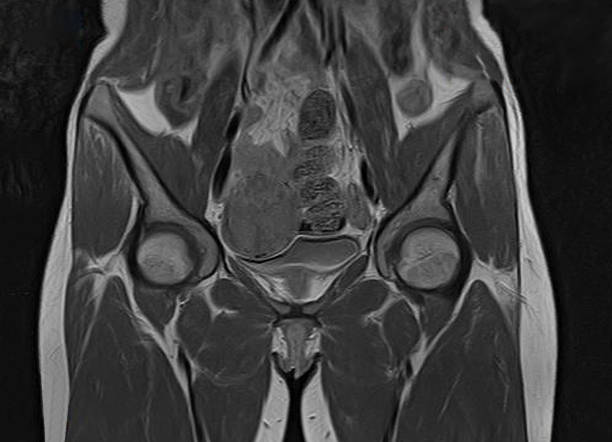

자궁근종(Uterine fibroids)은 여성의 자궁 내에 발생하는 양성 종양으로, 자궁 내막이나 근층에서 생길 수 있습니다. 대부분의 경우, 이 종양은 악성 종양이 아니며, 치료하지 않아도 괜찮은 경우가 많습니다. 그러나 증상이 심한 경우, 치료가 필요할 수 있습니다. 자궁근종의 증상은 그 크기와 위치에 따라 다릅니다. 아무런 증상이 없는 경우도 있지만, 대개는 다음과 같은 증상을 보일 수 있습니다.